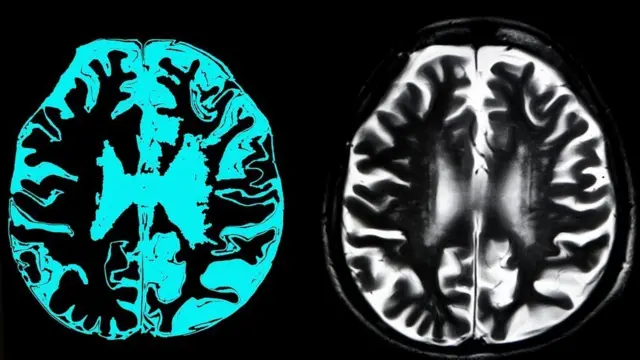

చనిపోయిన నాలుగు గంటల తర్వాత.. పంది మెదడు పాక్షిక పునరుద్ధరణ

జీవన్మరణాల మధ్య ఉండే రేఖ 2019లో అస్పష్టంగా మారింది.

పందులను చంపిన తర్వాత.. నాలుగు గంటల అనంతరం వాటి మెదళ్లను పాక్షికంగా పునరుద్ధరించారు.

మెదడు కణాల మరణాన్ని నిలిపివేయచ్చునని.. మెదడులోని కొన్ని అనుసంధానాలను పునరుద్ధరించవచ్చునని ఈ అధ్యయనం చూపింది.

జంతువుల శరీరం నుంచి వేరు చేసిన మెదళ్లకు.. సింథటిక్ రక్తాన్ని లయబద్ధంగా పంపించటం ద్వారా ఈ ప్రయోగం నిర్వహించారు.

మెదడుకు రక్త సరఫరా నిలిచిపోయిన నిమిషాల వ్యవధిలోనే మెదడు శాశ్వతంగా క్షీణించటం మొదలవుతుందనే భావనను సవాల్ చేస్తున్న ఈ ఆశ్చర్యకర ఫలితాలు.. మెదడు దెబ్బతినటం సహా ఇతరత్రా మెదడు వ్యాధులకు కొత్త చికిత్సలకు దారిచూపగలవు.

అయితే.. మెదడులో అవగాహన లేదా స్పృహ ఉందని సూచించే సంకేతాలేవీ కనిపించలేదు.